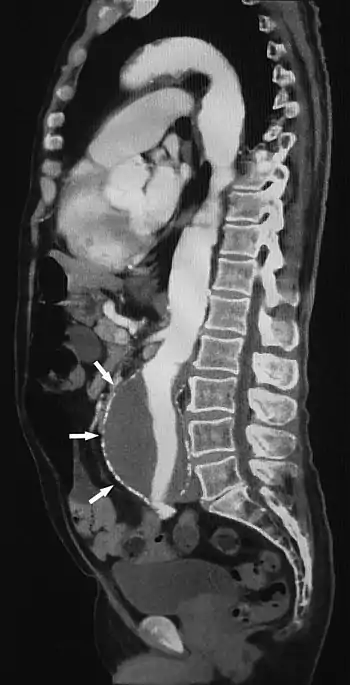

سی تی آنژیوگرافی (CTA) نوعی مقطعنگاری رایانهای است که روشی است برای تصویربرداری از عروق شریانی و وریدی(سی تی ونوگرافی) در سر تا سر بدن؛ از شریانهای تغذیهکننده مغز گرفته تا آنهایی که خون را به ریهها، کلیهها، دستها و پاها میرسانند. از این روش برای تشخیص میزان گرفتگی عروق، آنوریسم، ترومبوز، آمبولی، سودوآنوریسم، دایسکشن، فیستول شریانی-وریدی و... استفاده میشود.[1]

سی تی آنژیوگرافی در ارزیابی عروق خونی و اندامهایی که توسط آنها تغذیه میشوند، کاربرد دارد. این اندامها عبارتند از: مغز، قلب، لگن، گردن، قفسه سینه، پاها و انگشتان، بازوها و دستها، شکم (کلیهها و کبد)

پزشکان از سی تی آنژیو برای تشخیص و ارزیابی بسیاری از بیماریهای عروق خونی یا شرایط وابسته به آنها استفاده میکنند. این ارزیابیها شامل موارد زیر است: تومورها، جراحات، گرفتگی، آنوریسمها، پارگی عروق، لختههای خونی، رگهای خونی نامنظم مانند انواع ناهنجاریهای عروق، ناهنجاریهای مادرزادی (مربوط به زمان تولد) سیستم قلبی- عروقی[2]